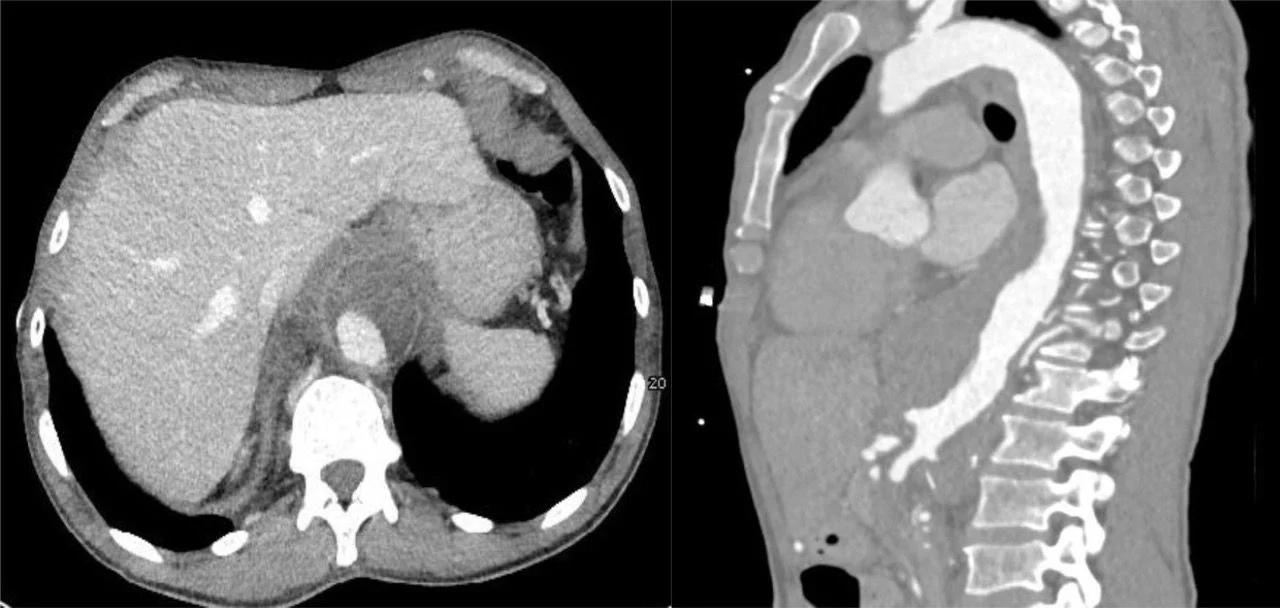

”Coexistence of chronic aortoiliac occlusion and mycotic aortic pathology expands the spectrum of vascular complications associated with IDU and thrombophilia.

Article: Collateral anastomosis in Leriche syndrome complicated by presumed mycotic thoracoabdominal aneurysm

Authors: Alexandros Apostolou, Maria Kadditi, Ilias G. Koziakas, Abdallah Aburub, Matthias Eberhard